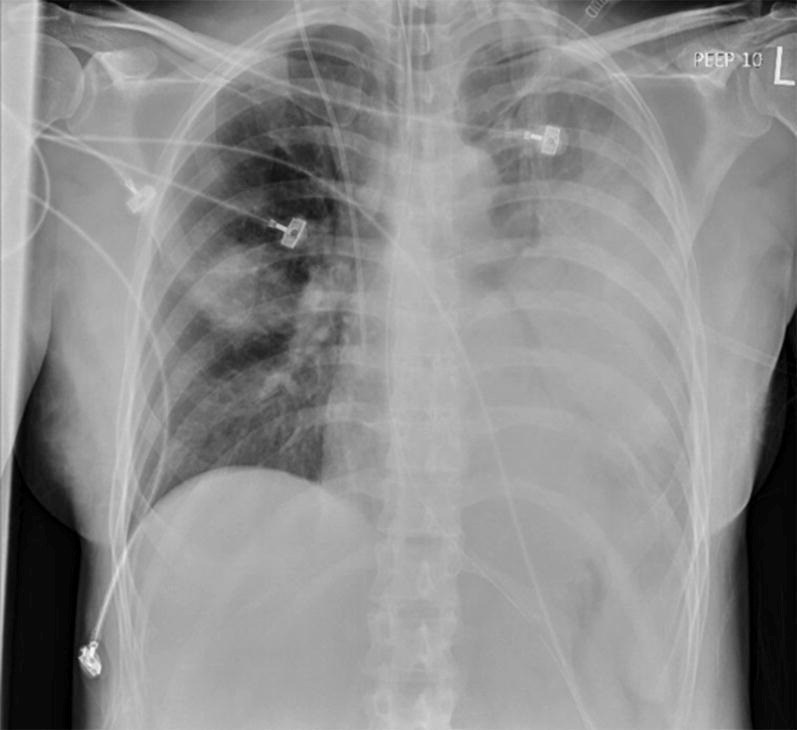

Radiografi toraks adalah pemeriksaan esensial untuk menegakkan diagnosis CAP. Pemeriksaan fisik untuk mendeteksi rales atau suara napas bronkial tidak cukup sensitif maupun spesifik. Foto toraks tidak hanya mengkonfirmasi adanya infiltrat paru tetapi juga membantu menyingkirkan diagnosis banding seperti gagal jantung kongestif atau emboli paru, serta menilai tingkat keparahan (misalnya, adanya infiltrat multilobar, yang merupakan salah satu kriteria minor IDSA/ATS).

Gambar 1. Foto thorax Pneumonia berat terintubasi dengan ventilator